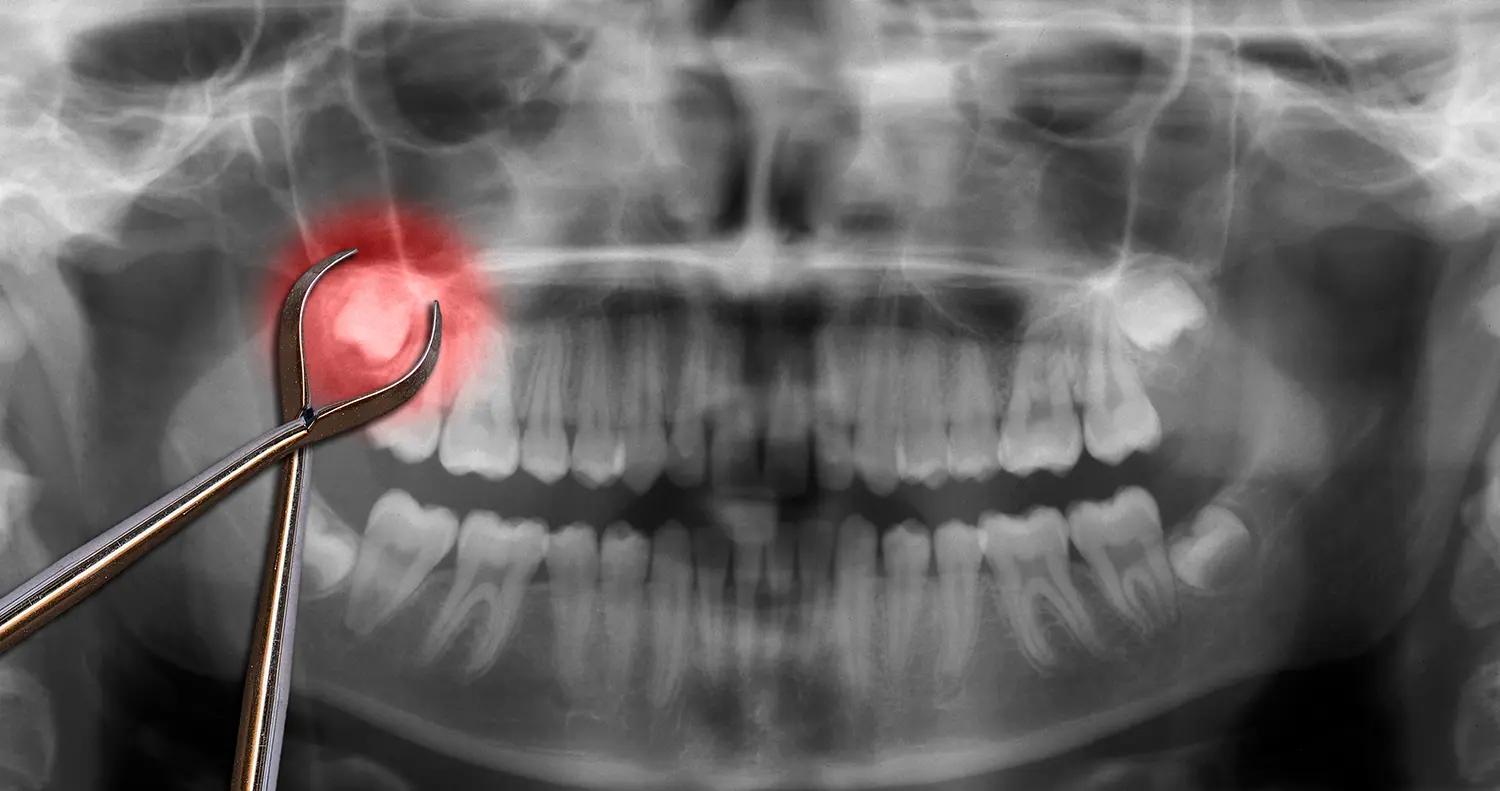

Wisdom Tooth (Third Molar) Extractions

Impacted or infected wisdom teeth are a common cause of dental emergencies. When these back molars don’t have enough room to erupt properly, they can cause pain, swelling, and infection.

Dr. Blackburn provides third molar extractions in-office using a gentle, methodical approach. With local anesthesia and optional sedation, you’ll stay comfortable and relaxed throughout the procedure.